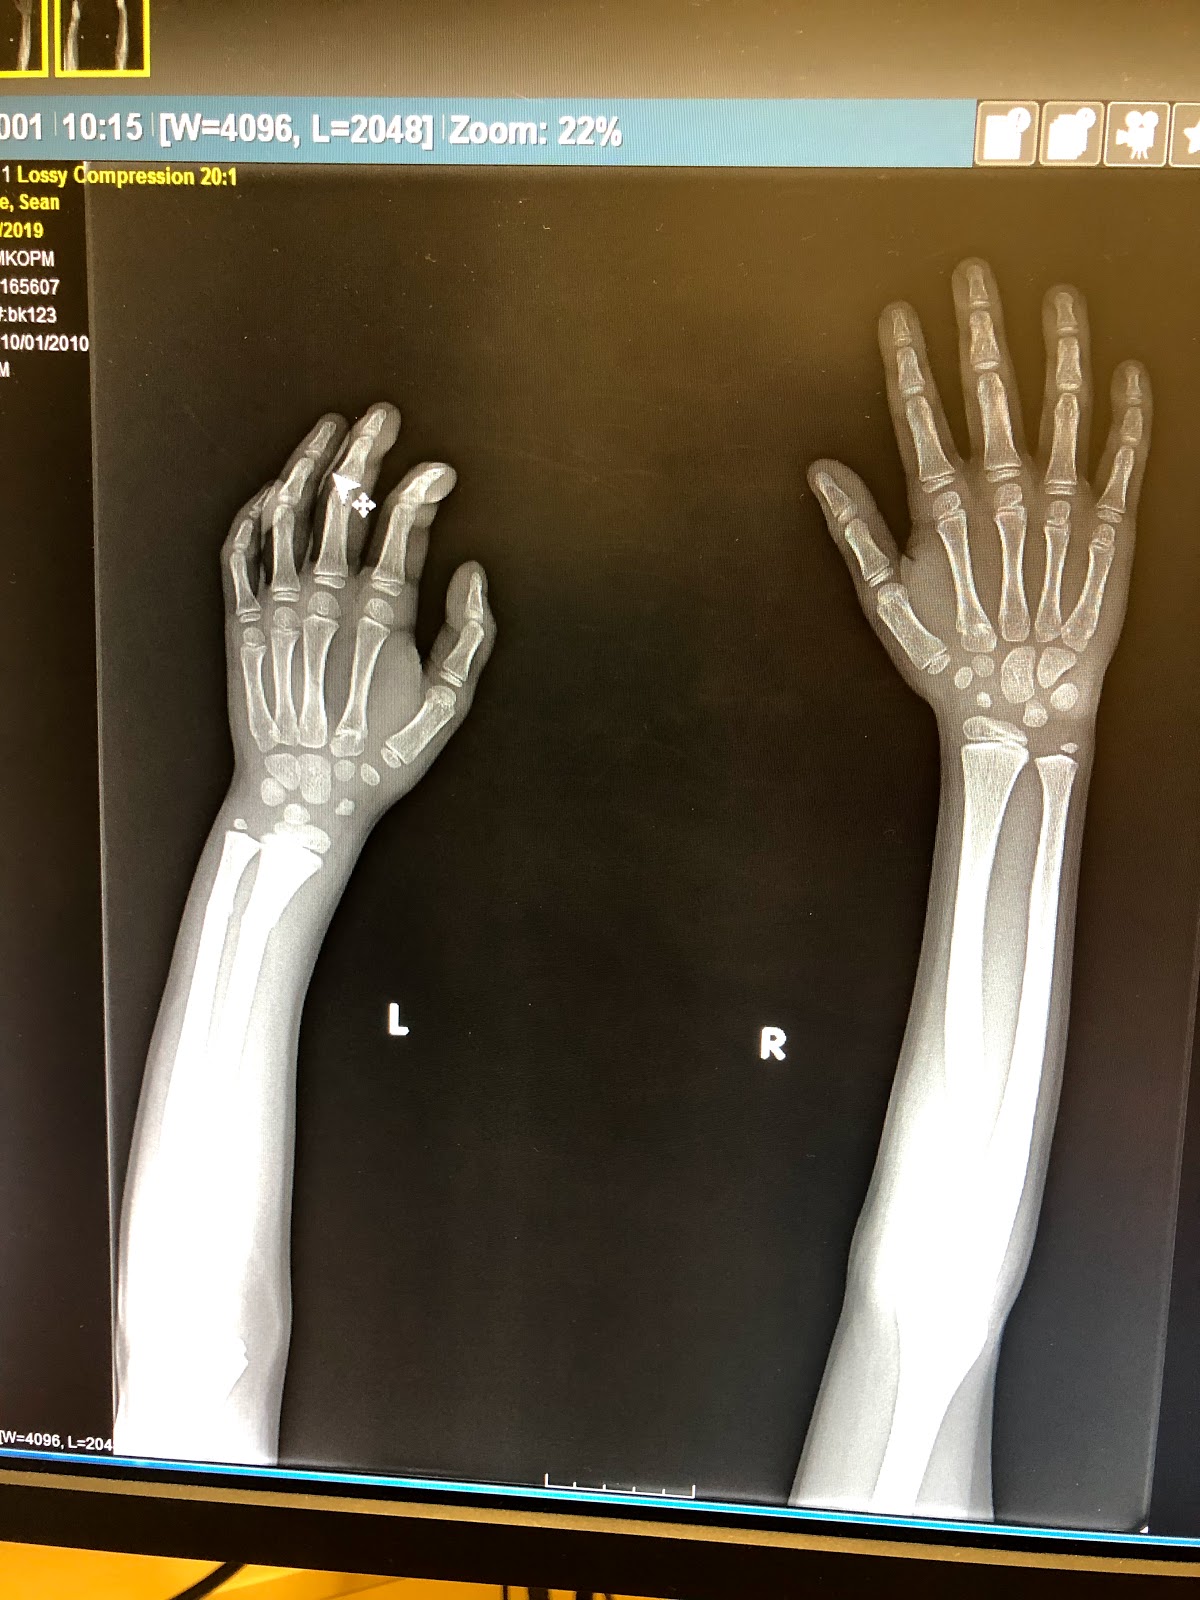

The next morning it still didn't look right. It was swollen and seemed bent to me. I decided to let him skip swim and took him to urgent care. After x-rays they confirmed that he broke both bones in his arm and would need a cast. They wrapped it up in a splint and ace bandage until we could get into the orthopedist later in the day. Luckily, the orthopedist we called was able to get us in that day since we were leaving for camping the next day.

The orthopedist was very quick with everything. They did another set of x-rays zooming in to the broken bones and put a light blue cast on his arm. He had to wear it for four weeks and avoid most fun activities (bike riding, scooter, swimming, and the trampoline).